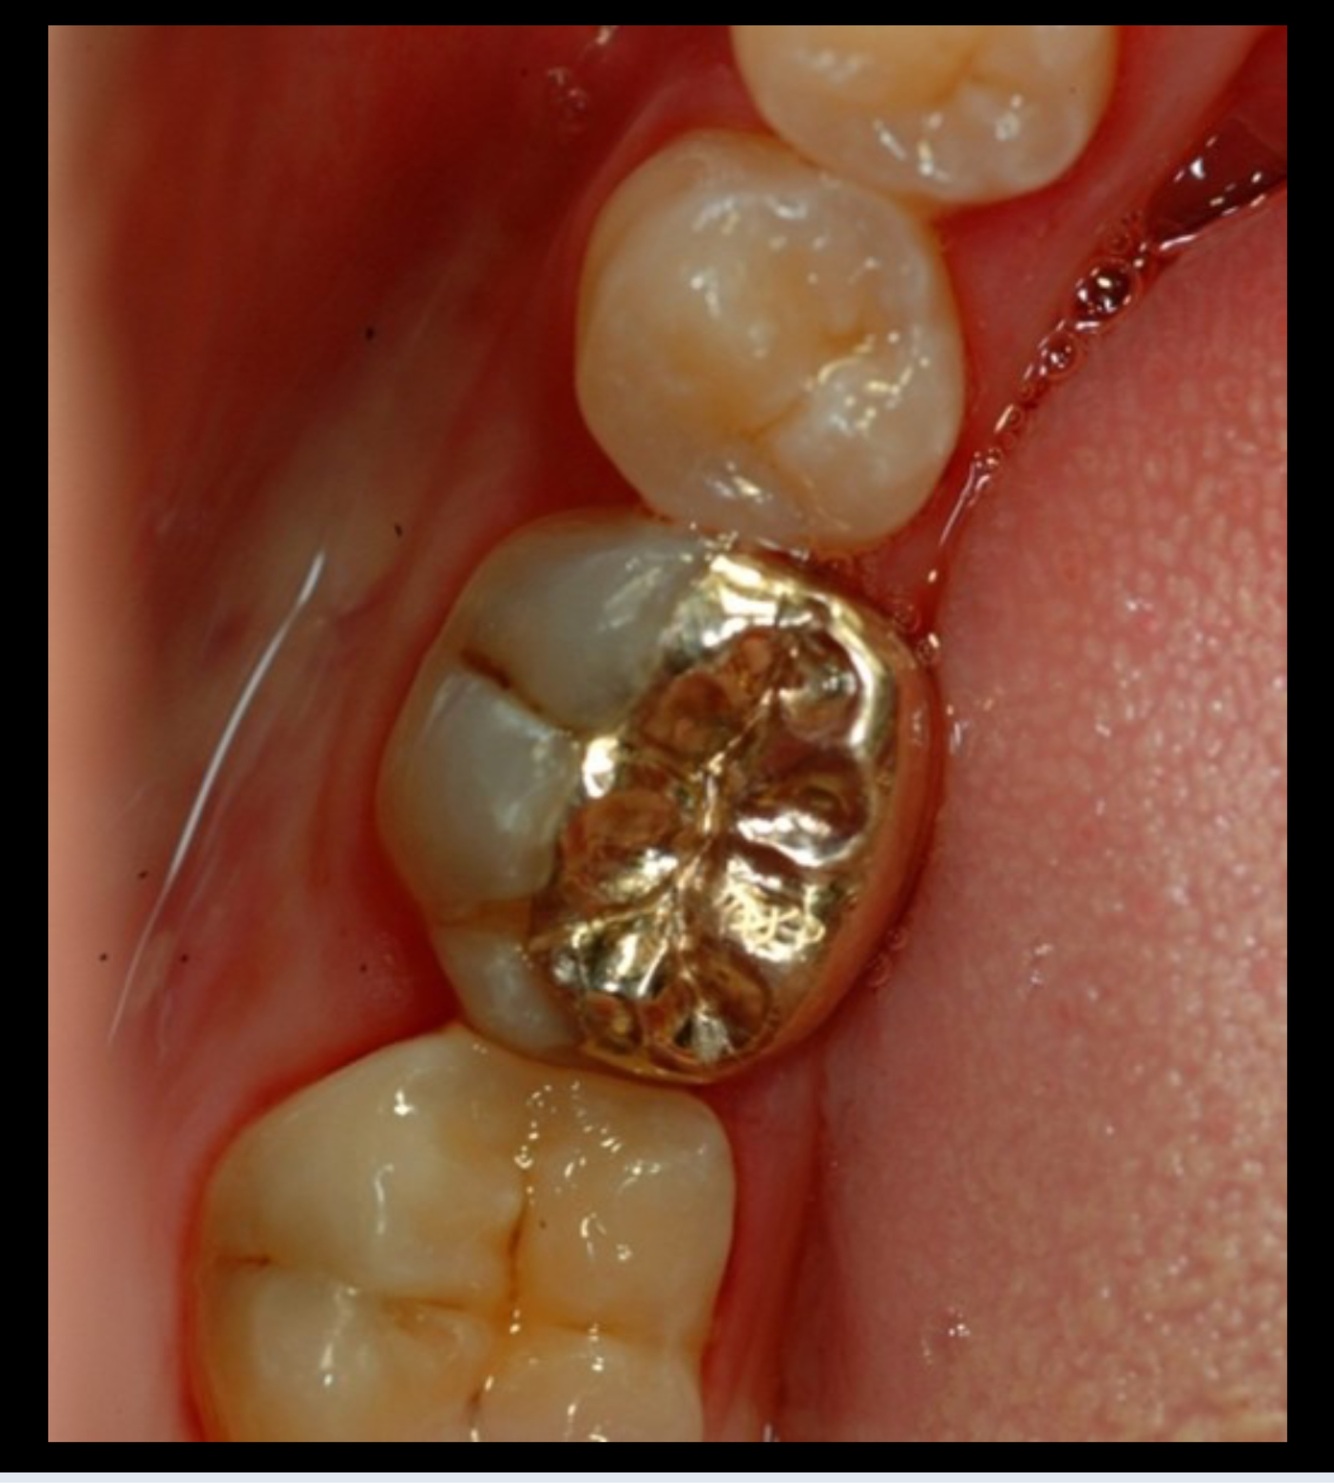

15

Q

This gold restoration is replacing:

This gold restoration is replacing

The palatal cusps of an upper 7

The lingual cusps of a lower 6

The buccal cusps of a lower 7

A